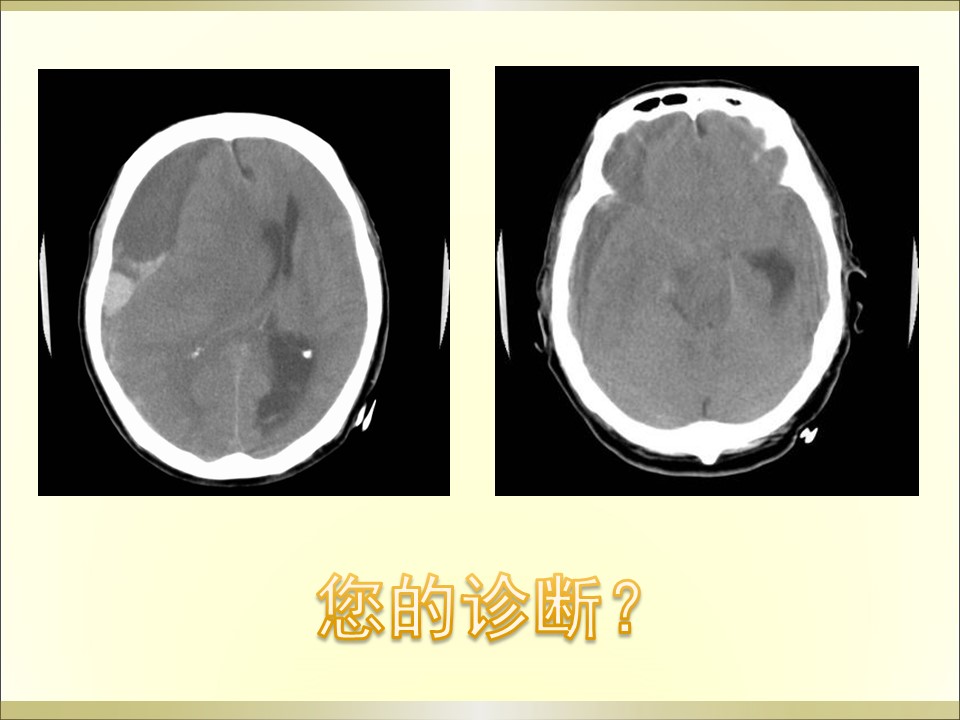

“脑疝的分类及影像表现” 的相关文章